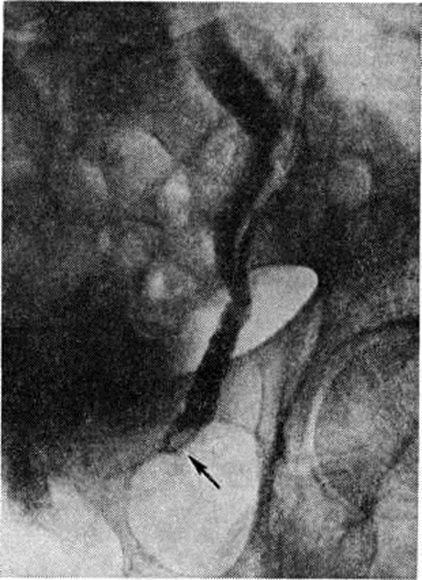

Рис. 3.

Рентгенограммы брюшной полости и таза больного почечнокаменной болезнью: а обзорная рентгенограмма, в лоханке правой почки стрелкой указана округлая тень камня; о экскреторная урограмма, видны расширенные чашечки и лоханка правой почки; дефект наполнения, обусловленный камнем, указан стрелкой.

Рентгенологические метод является основным в диагностике Почечнокаменная болезнь Он позволяет выявить не только наличие камней, но и установить их форму, величину, локализацию, структуру, а также получить представление об изменениях в анатомо-функциональном состоянии почек и мочевых путей. Исследование начинают с обзорной рентгенографии брюшной полости, начиная от ThXl до лонного сочленения. Обнаружение на обзорной рентгенограмме тени, подозрительной на конкремент, не требует дифференциальной диагностики только в случае коралловидного камня, являющегося слепком чашечно-лоханочной системы (рисунок 2). Камни почечных чашечек представляют собой их слепки или имеют неправильную, округлую форму; камни почечной лоханки часто округлые или треугольные; камни мочеточника — цилиндрической, веретенообразной или неправильной формы. При аномалиях мочевых путей конкремент может находиться вне обычной локализации почек и других органов мочеполовой системы. Обнаружение камня на снимке зависит от его размеров, химический состава и локализации. Наиболее интенсивное изображение дают оксалаты, затем камни смешанного состава и фосфаты. Оксалаты имеют шиповидные, фестончатые контуры и напоминают тутовую ягоду. Коралловидные камни чаще всего компактны, но могут быть слоистыми, как и остальные конкременты смешанного состава, иногда они достигают гигантских размеров. Слоистое строение камней на рентгенограммах обусловлено различной проницаемостью для рентгеновского излучения составляющих их солей. Около 10% камней с низким атомным весом (ураты, белковые, цистиновые и ксантиновые камни) не видны или дают неотчётливую тень. Особенно трудно выявить камни, проецирующиеся на костный скелет (ребра, поперечные отростки позвонков, крестцово-подвздошные сочленения). Для их обнаружения производят прицельные снимки в косых и атипичных проекциях, томо или зонографию. Томография (смотри полный свод знаний), применяемая самостоятельно или в сочетании с контрастными исследованиями, показана при недостаточной подготовке больного к рентгенологическое исследованиям, почечной колике, сопровождающейся парезом кишечника, или при малых размерах камней. Поскольку при Почечнокаменная болезнь довольно часто конкременты самопроизвольно отходят из чашечно-лоханочной системы, они могут проецироваться по ходу мочеточника паравертебрально, имеют тенденцию задерживаться над одним из его анатомических сужений. Наиболее важные сведения о принадлежности выявленной тени к мочевым путям, о локализации камня, вызванных им нарушениях функции почек, уродинамики, анатомического состояния мочевых путей (гидрокаликоз, пиелэктазия, гидроуретеронефроз — расширение чашечек, лоханки, мочеточника и почки) выявляются при экскреторной урографии (рисунок 3, б) с предварительной обзорной рентгенографией (рисунок 3, а). Она позволяет установить вид лоханки (открытая или закрытая, внутрипочечная или внепочечная), состояние лоханочно-мочеточникового сегмента (смотри полный свод знаний: Пиелография). Обычно рентгенопозитивный конкремент определяется в мочевых путях, но иногда его изображение перекрывается, как бы тонет на фоне контрастированной мочи, особенно при небольшом камне или малой интенсивности его изображения. При рентгенонегативных камнях виден дефект наполнения мочевых путей (в том числе и лоханки) с чёткими контурами (рисунок 4). В отличие от опухоли лоханки в косых проекциях вокруг камня сохраняется ободок контрастного вещества. Обычно при камнях лоханки, достигающих в диаметре 3 сантиметров и более, наблюдаются пиелэктазия и гидрокаликоз. Произведённые в процессе экскреторной урографии телевизионная пиелоуретероскопия в сочетании с кинематографией или видеомагнитофонной записью изображения позволяют оценить нарушения тонуса и моторной функции верхних мочевых путей при камнях, отличить спастические, функциональный процессы от органических. Если спустившийся в мочеточник камень частично закрывает его, то отмечаются расширение мочеточника и лоханки (пиелоуретерэктазия) выше уровня расположения конкремента. На экскреторных урограммах, произведённых во время почечной колики, выявляется увеличенная почка с усиленным нефрографическим эффектом без контрастирования чашечно-лоханочной системы и мочеточника — так называемый большая белая почка. Такая рентгенологическое картина указывает, что функция почки сохранена. При длительной полной блокаде камнем (более 3—4 недель) функция почки из-за атрофии снижается и может полностью утрачиваться. На экскреторных урограммах, произведённых после почечной колики, иногда наблюдается проникновение контрастированной мочи за пределы мочевых путей, а также лоханочно-почечный рефлюкс. Ретроградную пиелоуретерографию с жидким контрастным веществом или кислородом производят только при значительном снижении функции почек, при сомнении в диагнозе, особенно в тех случаях, когда при экскреторной урографии не выявляется рентгенонегативный камень. Рентгенографию мочеточника после введения в него катетера производят в прямой и косой проекциях. Если при этом тень, подозрительная на камень, на обоих снимках находится рядом с катетером или сливается с его тенью, то диагноз Почечнокаменная болезнь не вызывает сомнений. Тень, не относящаяся к мочеточнику, определяется на некотором расстоянии от катетера. На ретроградных пиелограммах с жидким контрастным веществом небольшой концентрации рентгенонегативные камни выявляются в виде дефекта наполнения. Особенно демонстративными такие камни становятся при пневмопиелорентгенографии или пневмопиелотомографии (рисунок 5). С помощью ретроградной уретерографии удаётся выявить рентгенонегативный камень в мочеточнике, верхние границы дефекта при этом имеют вогнутую форму (рисунок 6).